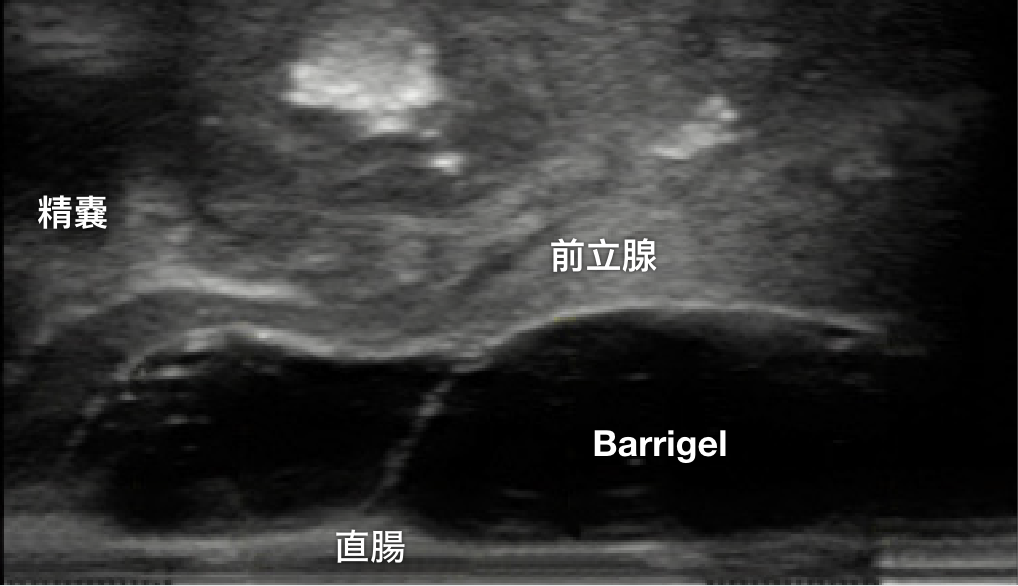

TRUS 画像

TRUS画像提供:Rizwan Nurani, MD

Radiation Oncologist; California, United States